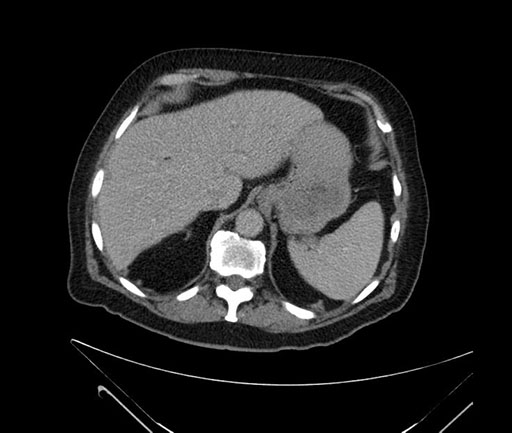

Imaging Analysis

Look through the patient's CT scan to identify any areas of concern for the necessary procedure.

Based on your CT findings, which issue(s) would give reason for "planned slowing down moment(s)" in this case?